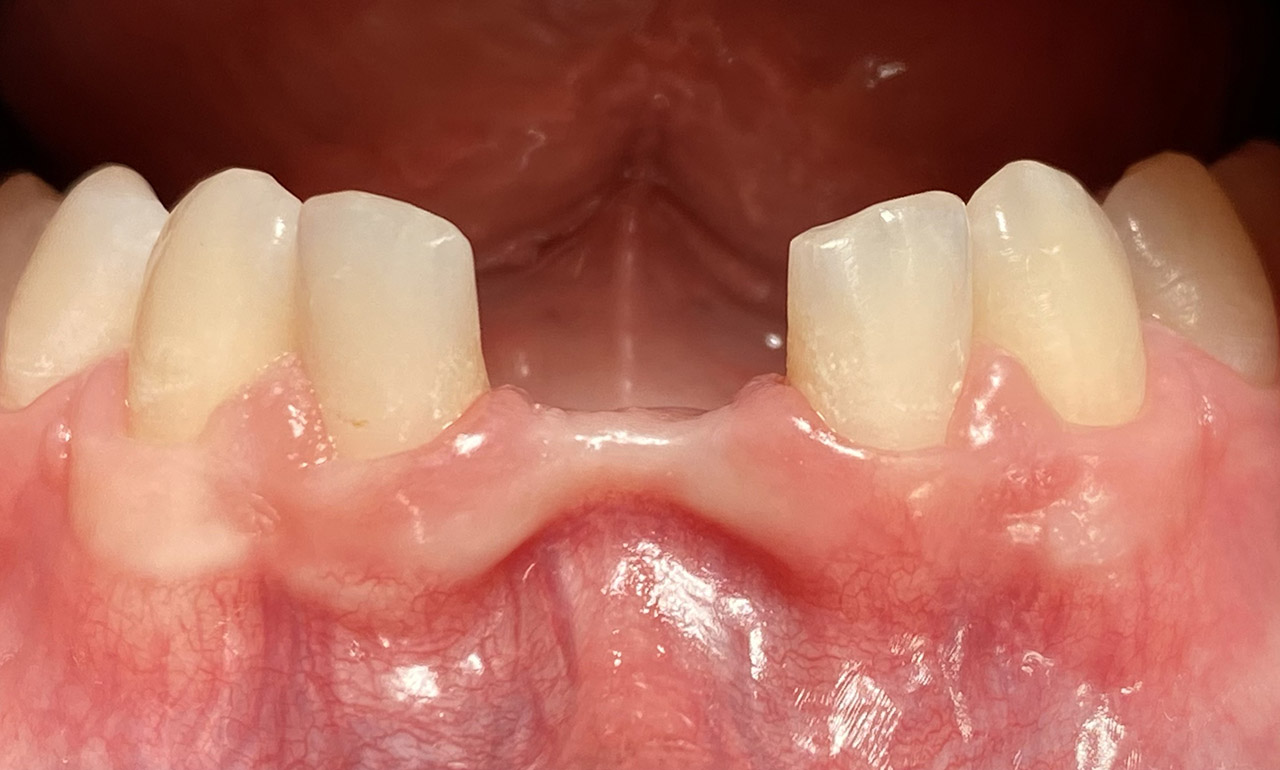

Traumatologie und Endodontie:

Nach Unfall/Sturz mittlerer Schneidezahn auf Gingivaniveau abgebrochen, Pulpa weit eröffnet, beide Nachbarzähne ebenfalls frakturiert.

Erstversorgung: Pulpektomie der Kronenpulpa, MTA, provisorischer Verschluß mit rosa Glasionomerfüllung.

Wiederaufbau der Nachbarzähne mit mitgebrachten (plus 1 Stein) Zahnstücken mit Kunststoff ergänzt und adhäsiv verklebt.

2. Schritt nach Aushärtung von MTA: Entfernung der Kronenpulpa im Bruchstück zur Vermeidung von Verfärbung, Füllung mit Kunststoff.

Adhäsives zementieren des abgebrochenen Zahnstücks.